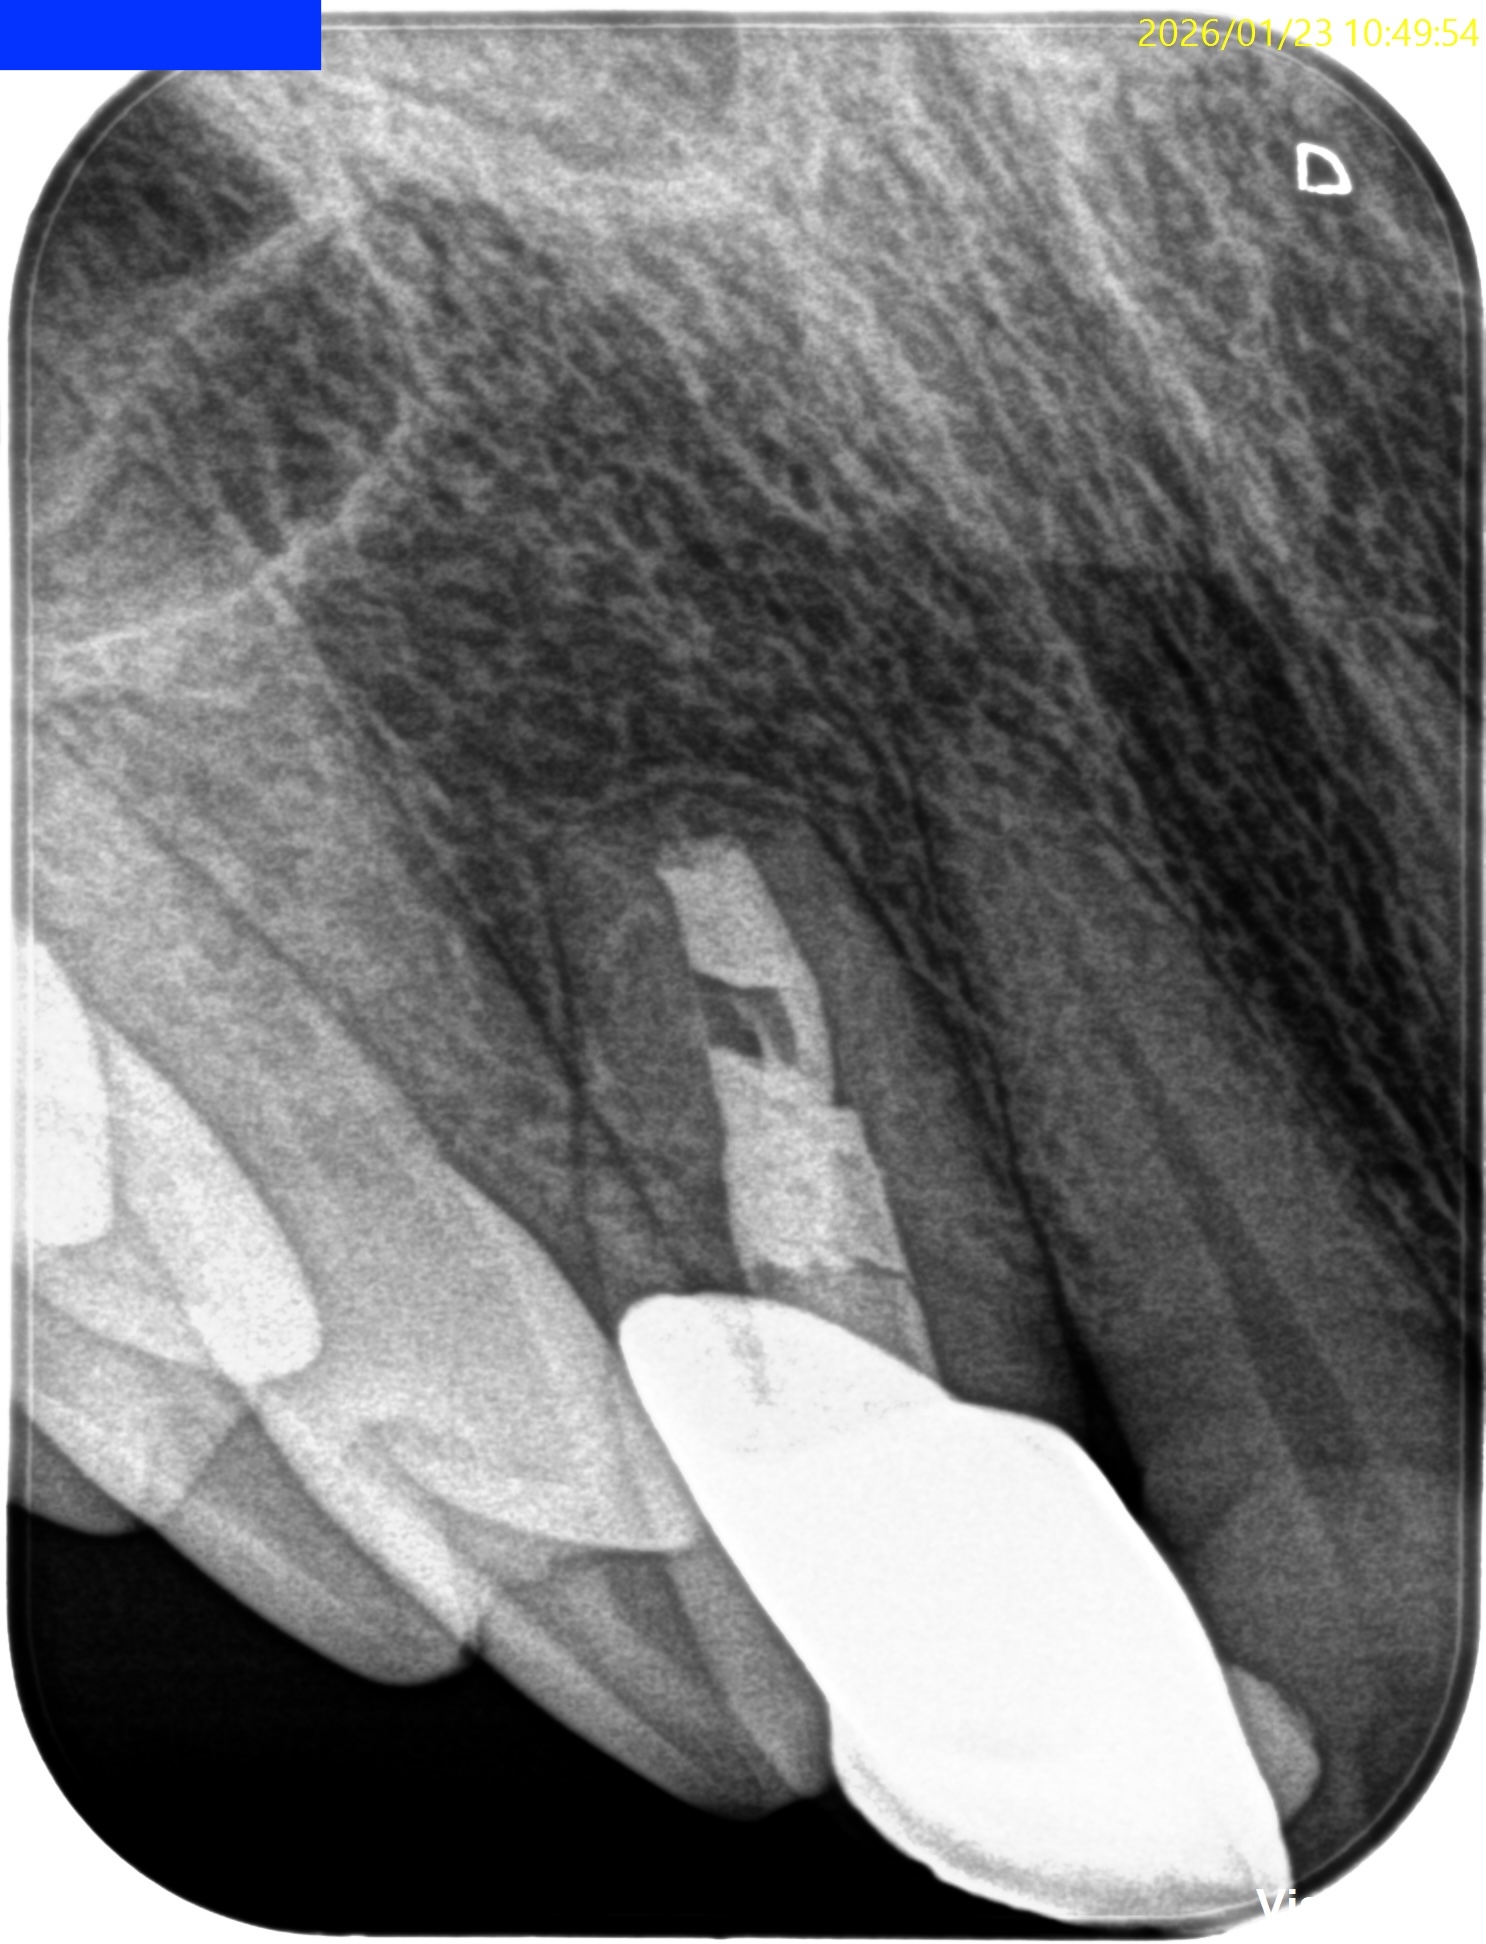

上顎前歯は麻酔の効果時間が短いため時短で縫合し終了できるSubmarhginal Flapを選択したのでその方法で行った。

4分で#7のApexまで到達し、

2分で根切し、

3分で逆根管形成と逆根管充填が終了している。

術後にPA, CBCTを撮影した。

気泡が逆根管充填材に混入したが、問題はないだろう。

初診時と比較した。

気泡は入ったが劇的に治癒し、臨床症状もないことからこの日で終診となった。